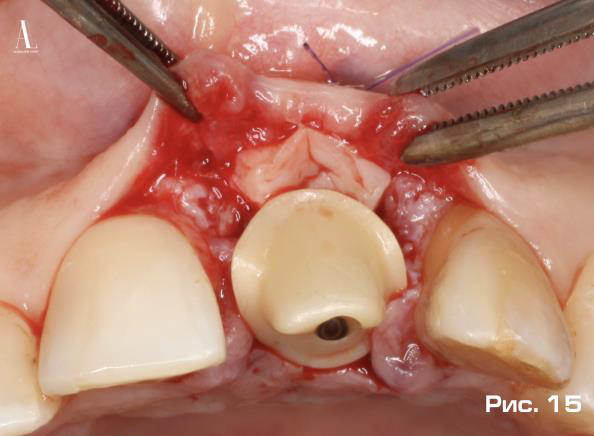

Дополнительное пространство, образованное между абатментом и вестибулярным мукопериостальным лоскутом, ис пользовалось для мягкотканной аугментации с применением свободного соединительнотканного аутотрансплантата, полученного из небной области по методике «Single-incision technique» предложенной Hurzeler M, Weng D в 1999 году (Рис. 14, 15).